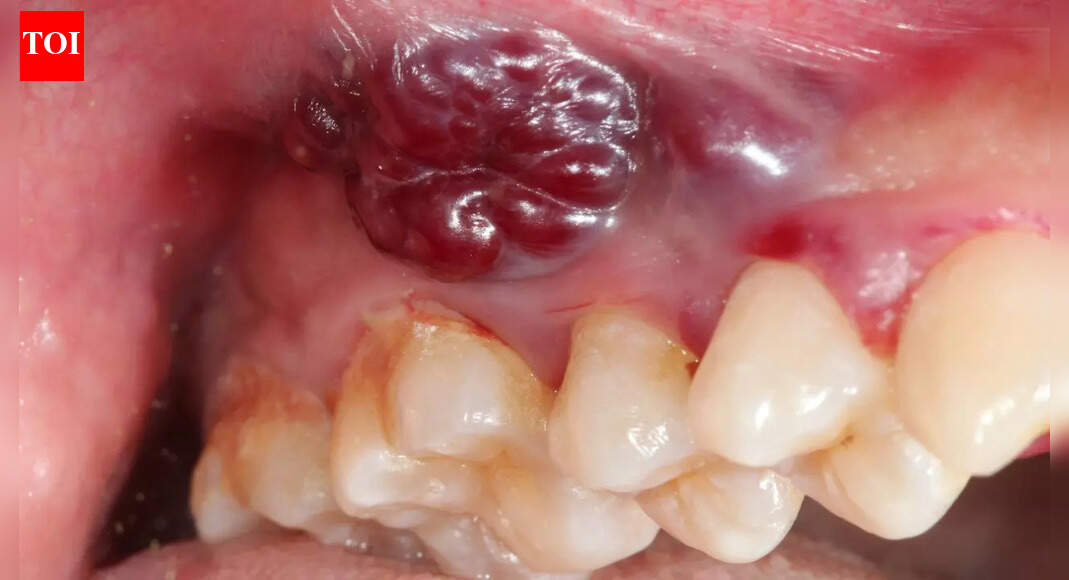

Indian women and growing oral cancer cases: Why a non-healing mouth ulcer could be the earliest red flag

A mouth ulcer is usually seen as a small irritation that appears after accidentally biting the inside of your cheek or eating spicy food when the body is stressed. Most people expect it to heal on its own within a few days and rarely think twice about it. However, for an increasing number of Indian»»»